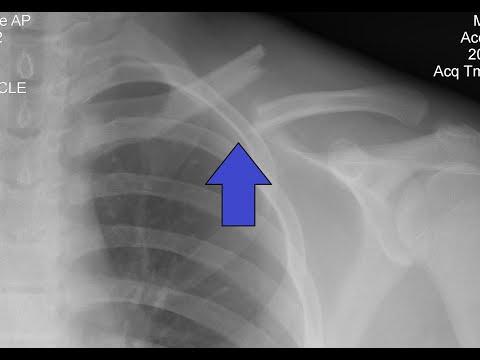

Перелом ключицы

перелом ключицы

Перелом ключицы со смещением и без. Когда нужна операция? Сколько срастается?

кратко о переломе ключицы